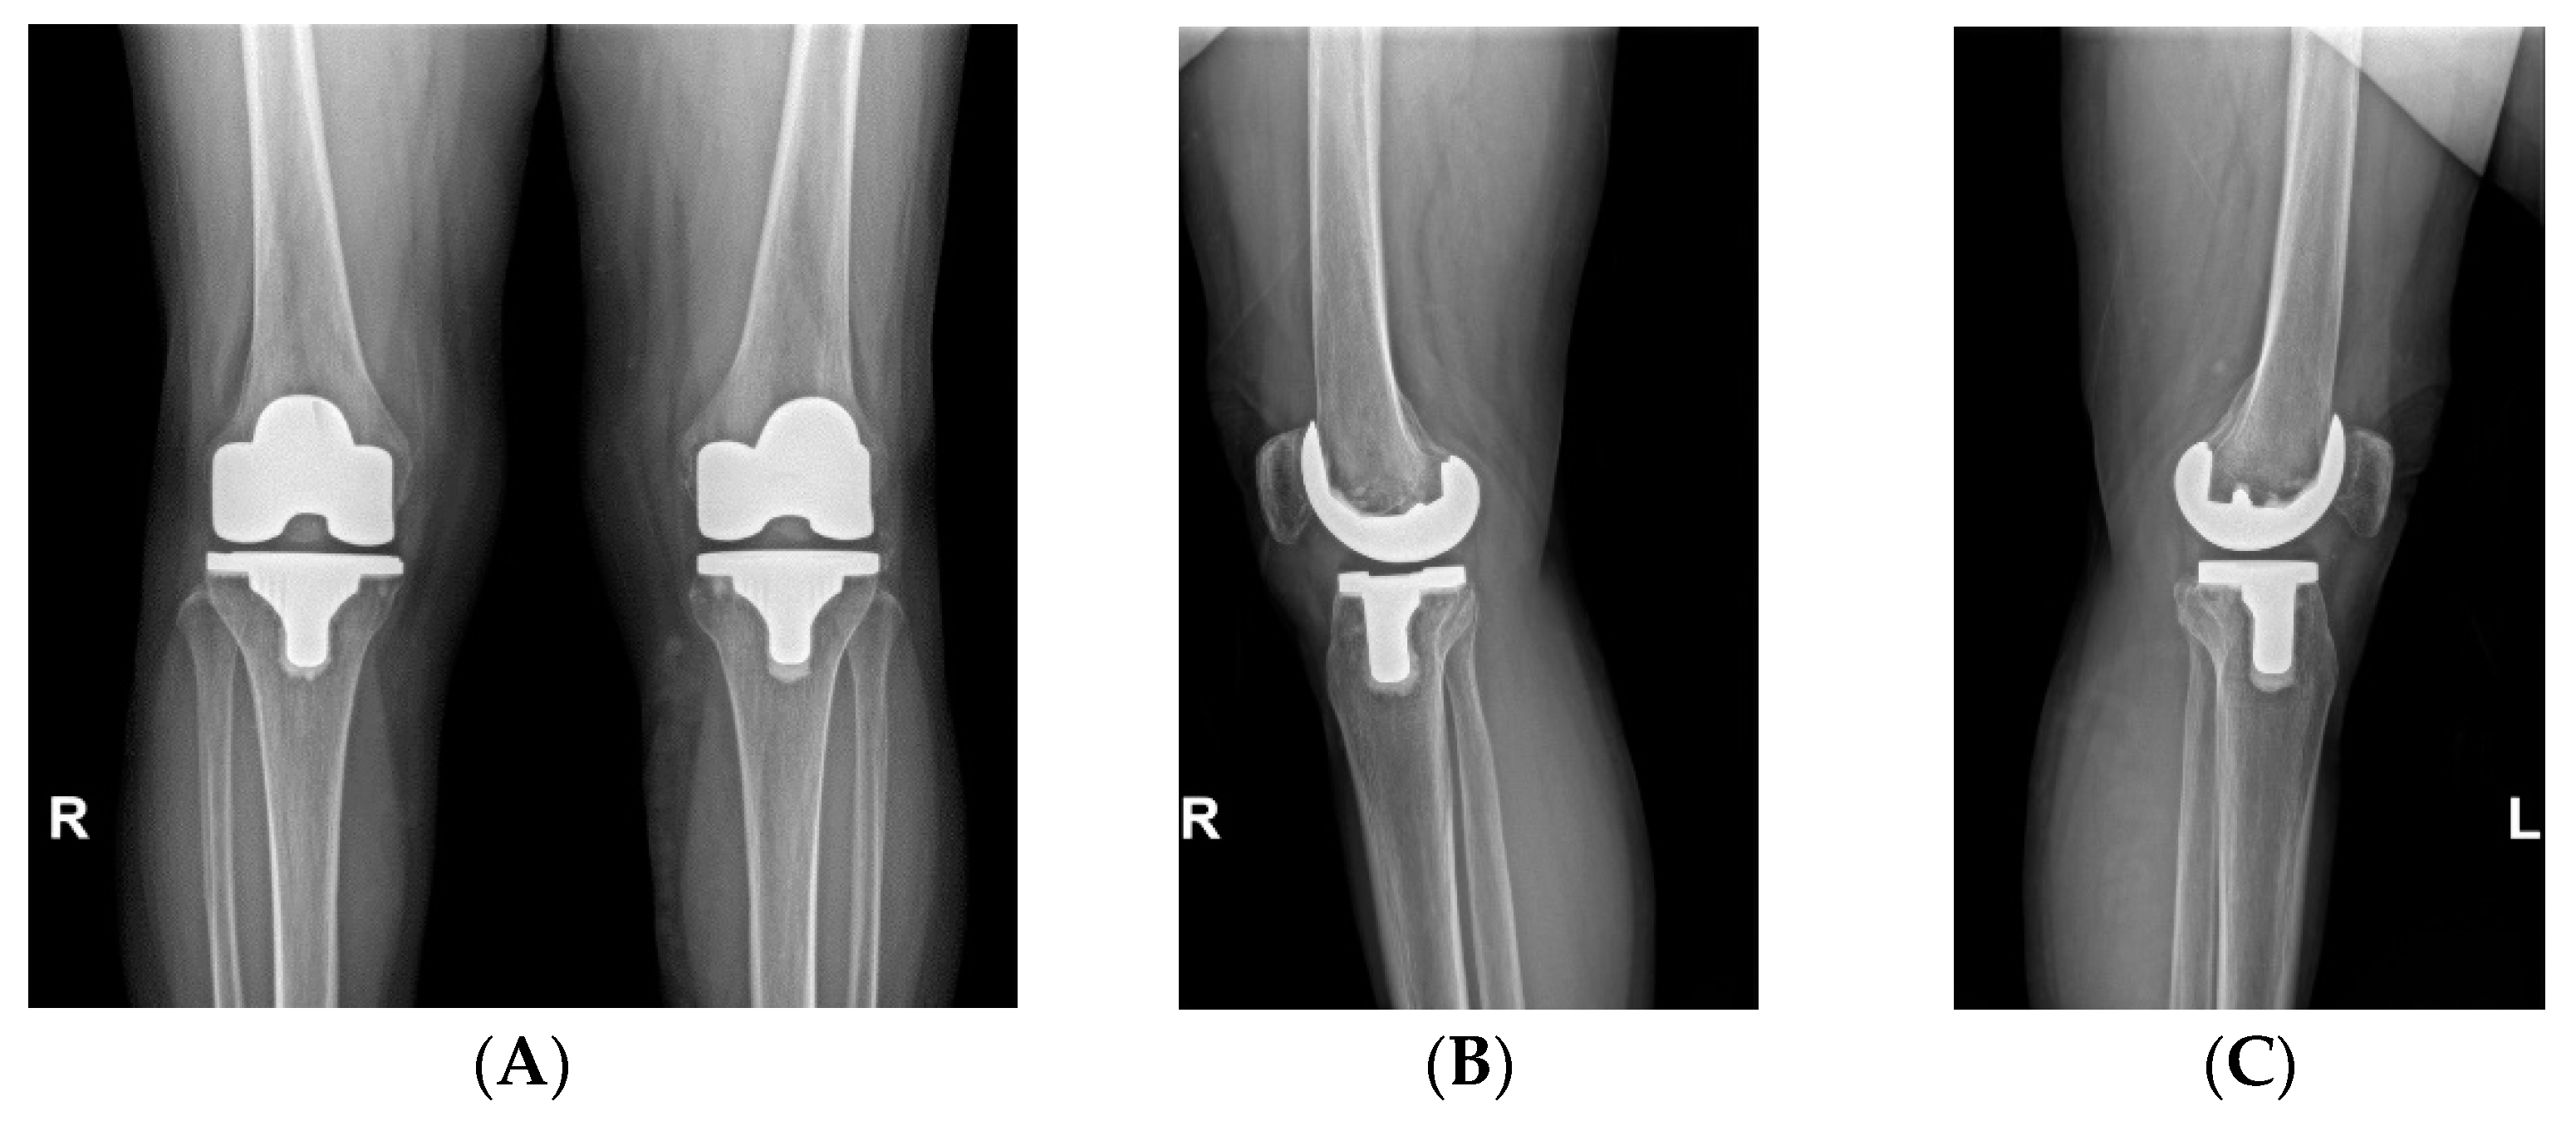

Can a Total Knee System Providing 1 mm Increment of Polyethylene Insert Thickness Offer a Clinical Benefit?

- Song, S.J.; Lee, H.W.; Park, C.H. A Current Prosthesis With a 1-mm Thickness Increment for Polyethylene Insert Could Result in Fewer Adjustments of Posterior Tibial Slope in Cruciate-Retaining Total Knee Arthroplasty. J. Arthroplast. 2020, 35, 3172–3179. [Google Scholar] [CrossRef]

| PE thickness, mm | 11.5 ± 1.8 | 12.8 ± 1.6 | 0.001 |

| PE thickness, mm (except three patients using 9 mm) Thick (≥13 mm) PE, n (%) Thick (≥14 mm) PE, n (%) Thick (≥15 mm) PE, n (%) | 11.6 ± 1.7 11 (23.4%) 6 (12.7%) 3 (6.4%) | 12.7 ± 1.8 18 (38.3%) 18 (38.3%) 5 (10.6%) | 0.008 0.118 0.005 0.714 |